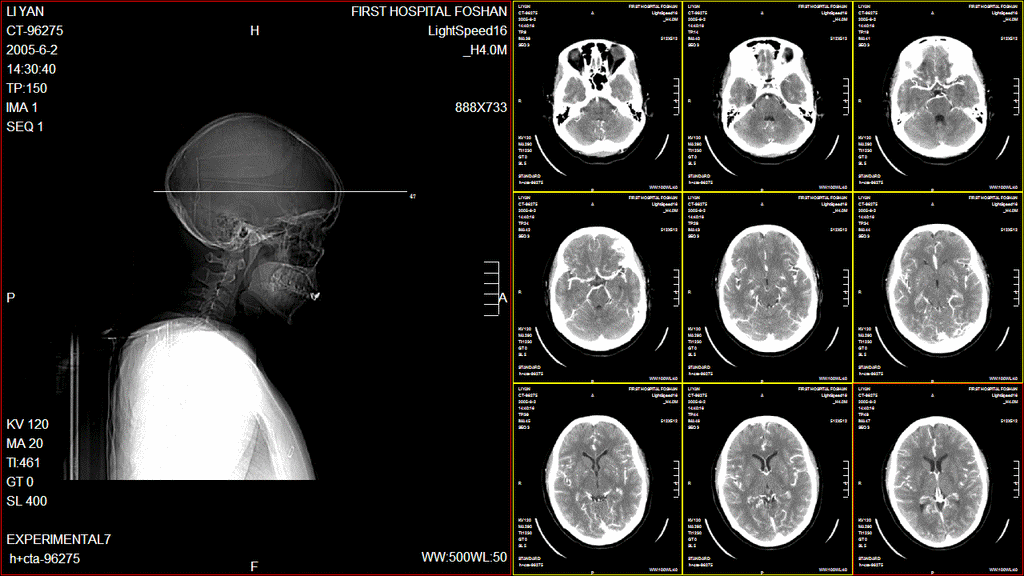

医生打开病人病历,能够在医用显示器上,对病人的检查图像进行诊断,可以选择打开检查的所有图像,也可以分不同的序列来打开。本平台支持双屏甚至三屏显示,可根据不同的影像类别,确定一屏多图不同的显示方式;可根据不同的检查部位,确定不同的窗宽窗位默认值。医生通过简单的操作,能够对图像进行各种处理,窗宽窗位、放大、体位线标注等等,大大提高了诊断效率。